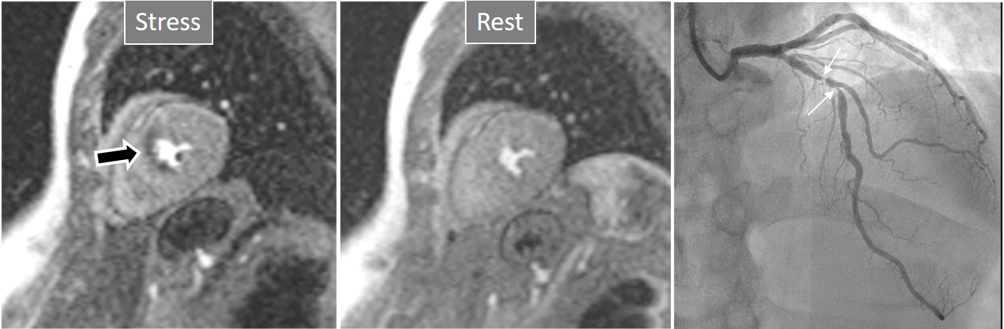

The aim of perfusion studies is the demonstration of a blunted increase—or a reduction—in regional MBF in response to a vasodilator stimulus which can be attributed to a flow-limiting coronary artery lesion. Rest perfusion studies alone are not useful in this sense, as basal MBF is kept within normal limits even in territories supplied by a severely stenosed vessel, and is only after a vasodilator agent has been given that the reduction in CFR can be evidenced [24]. In CMR studies, this situation is detected as a reduced increase in SI of the underperfused territories (Fig. 3).

Fig. 3.Induced perfusion defect. Subendocardial perfusion defect at the interventricular septum during stress (left panel, black arrow), not present at rest (middle panel), in a patient with significant coronary stenoses in the left anterior descending (LAD) artery (right panel, white arrows).